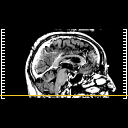

Click on sagittal image to select slice. Click on thin tickmark to change timepoint, or thick tickmark for overlay.